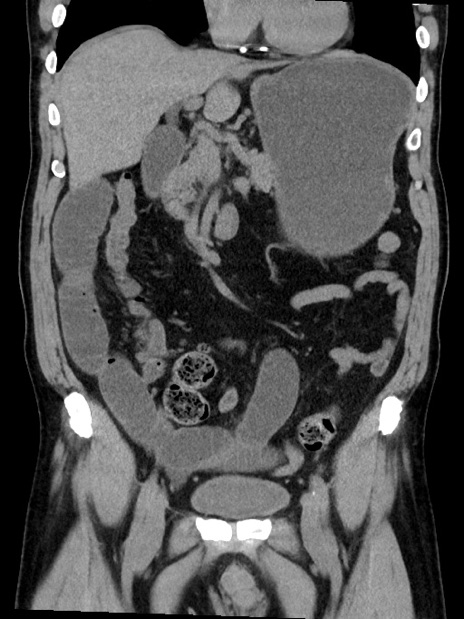

症例35(冠状断像)

【症例】70歳代 男性

【主訴】腹部膨満、嘔吐

【現病歴】昨日より腹部膨満感出現。本日増悪し、仙痛出現。嘔吐あり、受診。

【既往歴】糖尿病、胆摘後

【身体所見】BP 149/80mmHg、HR 74/min、BT 35.9℃、腹部:膨満、軟、圧痛なし。腸雑音減弱あり。上腹部正中切開瘢痕あり。

【データ】WBC 13500、CRP 1.72